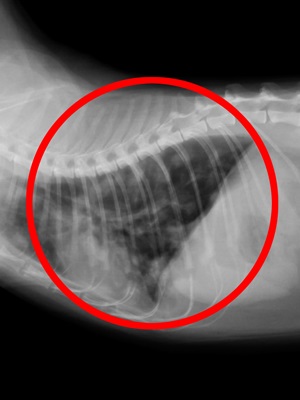

고양이의 비만세포종은 수술에 의한 절제가능 여부가 예후를 크게 좌우합니다 비만세포종은 사람에게는 거의 발생하지 않지만 개와 고양이에게는 빈번하게 발생하는 악성종양으로 개의 피부에 생기는 악성종양에서는 첫 번째로 많으며, 고양이에게는 두 번째로 많다고 보고되고 있습니다. 고양이의 비만세...